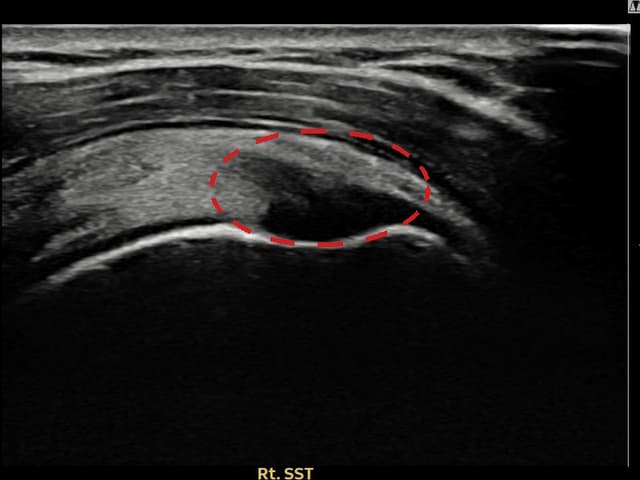

[촬영시기:22.09.19~22.12.09]

[어깨인대 축소봉합술] 우측 어깨 통증이 수개월간 지속되어 내원하셨습니다.